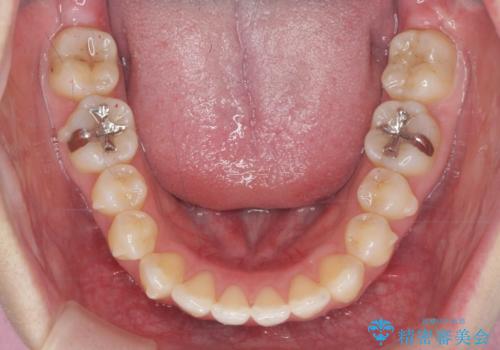

矯正治療後、前歯のがたつき、咬合関係が改善され満足いただくことができました。